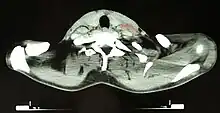

Hodgkin lymphoma must be distinguished from non-cancerous causes of lymph node swelling (such as various infections) and from other types of cancer. Definitive diagnosis is by lymph node biopsy (usually excisional biopsy with microscopic examination). Blood tests are also performed to assess function of major organs and to assess safety for chemotherapy. Positron emission tomography (PET) is used to detect small deposits that do not show on CT scanning. PET scans are also useful in functional imaging (by using a radiolabeled glucose to image tissues of high metabolism). In some cases a Gallium scan may be used instead of a PET scan.

Hodgkin lymphoma- hilum overlay sign